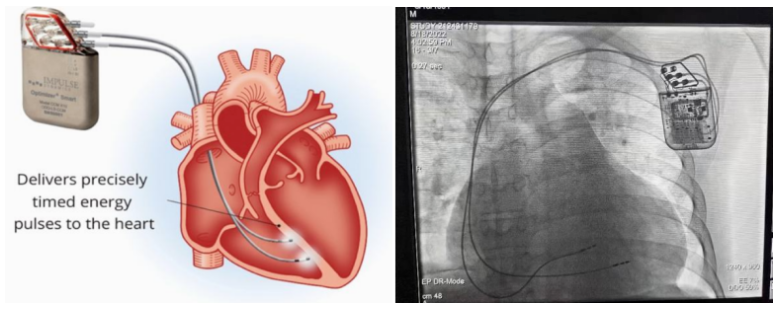

①植入式心臟復(fù)律除顫器

Implantable Cardioverter Defibrillator,ICD

植入式心臟復(fù)律除顫器是一種具有除顫功能的高級起搏器,是一種體積小、能植入患者胸部皮下組織的醫(yī)療設(shè)備。慢性心衰患者易發(fā)生室性心動過速或心室顫動,導(dǎo)致心源性猝死(SCD)。ICD 則能在幾秒內(nèi)自動識別并治療快速室性心律失常,通過低能量心臟轉(zhuǎn)復(fù)和高能量除顫等功能,顯著降低惡性室性心律失常引起的猝死風(fēng)險(xiǎn)??杉皶r自動為患者轉(zhuǎn)復(fù)心律,通俗地說就是裝在體內(nèi)的自動除顫儀。

國內(nèi)研發(fā)企業(yè):無雙醫(yī)療、邁瑞、魚躍、久心、微創(chuàng)、維偉思、麥邦等